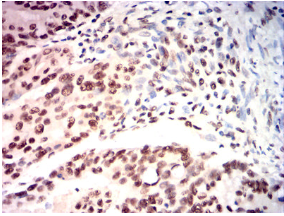

IHC    1/200 - 1/1000